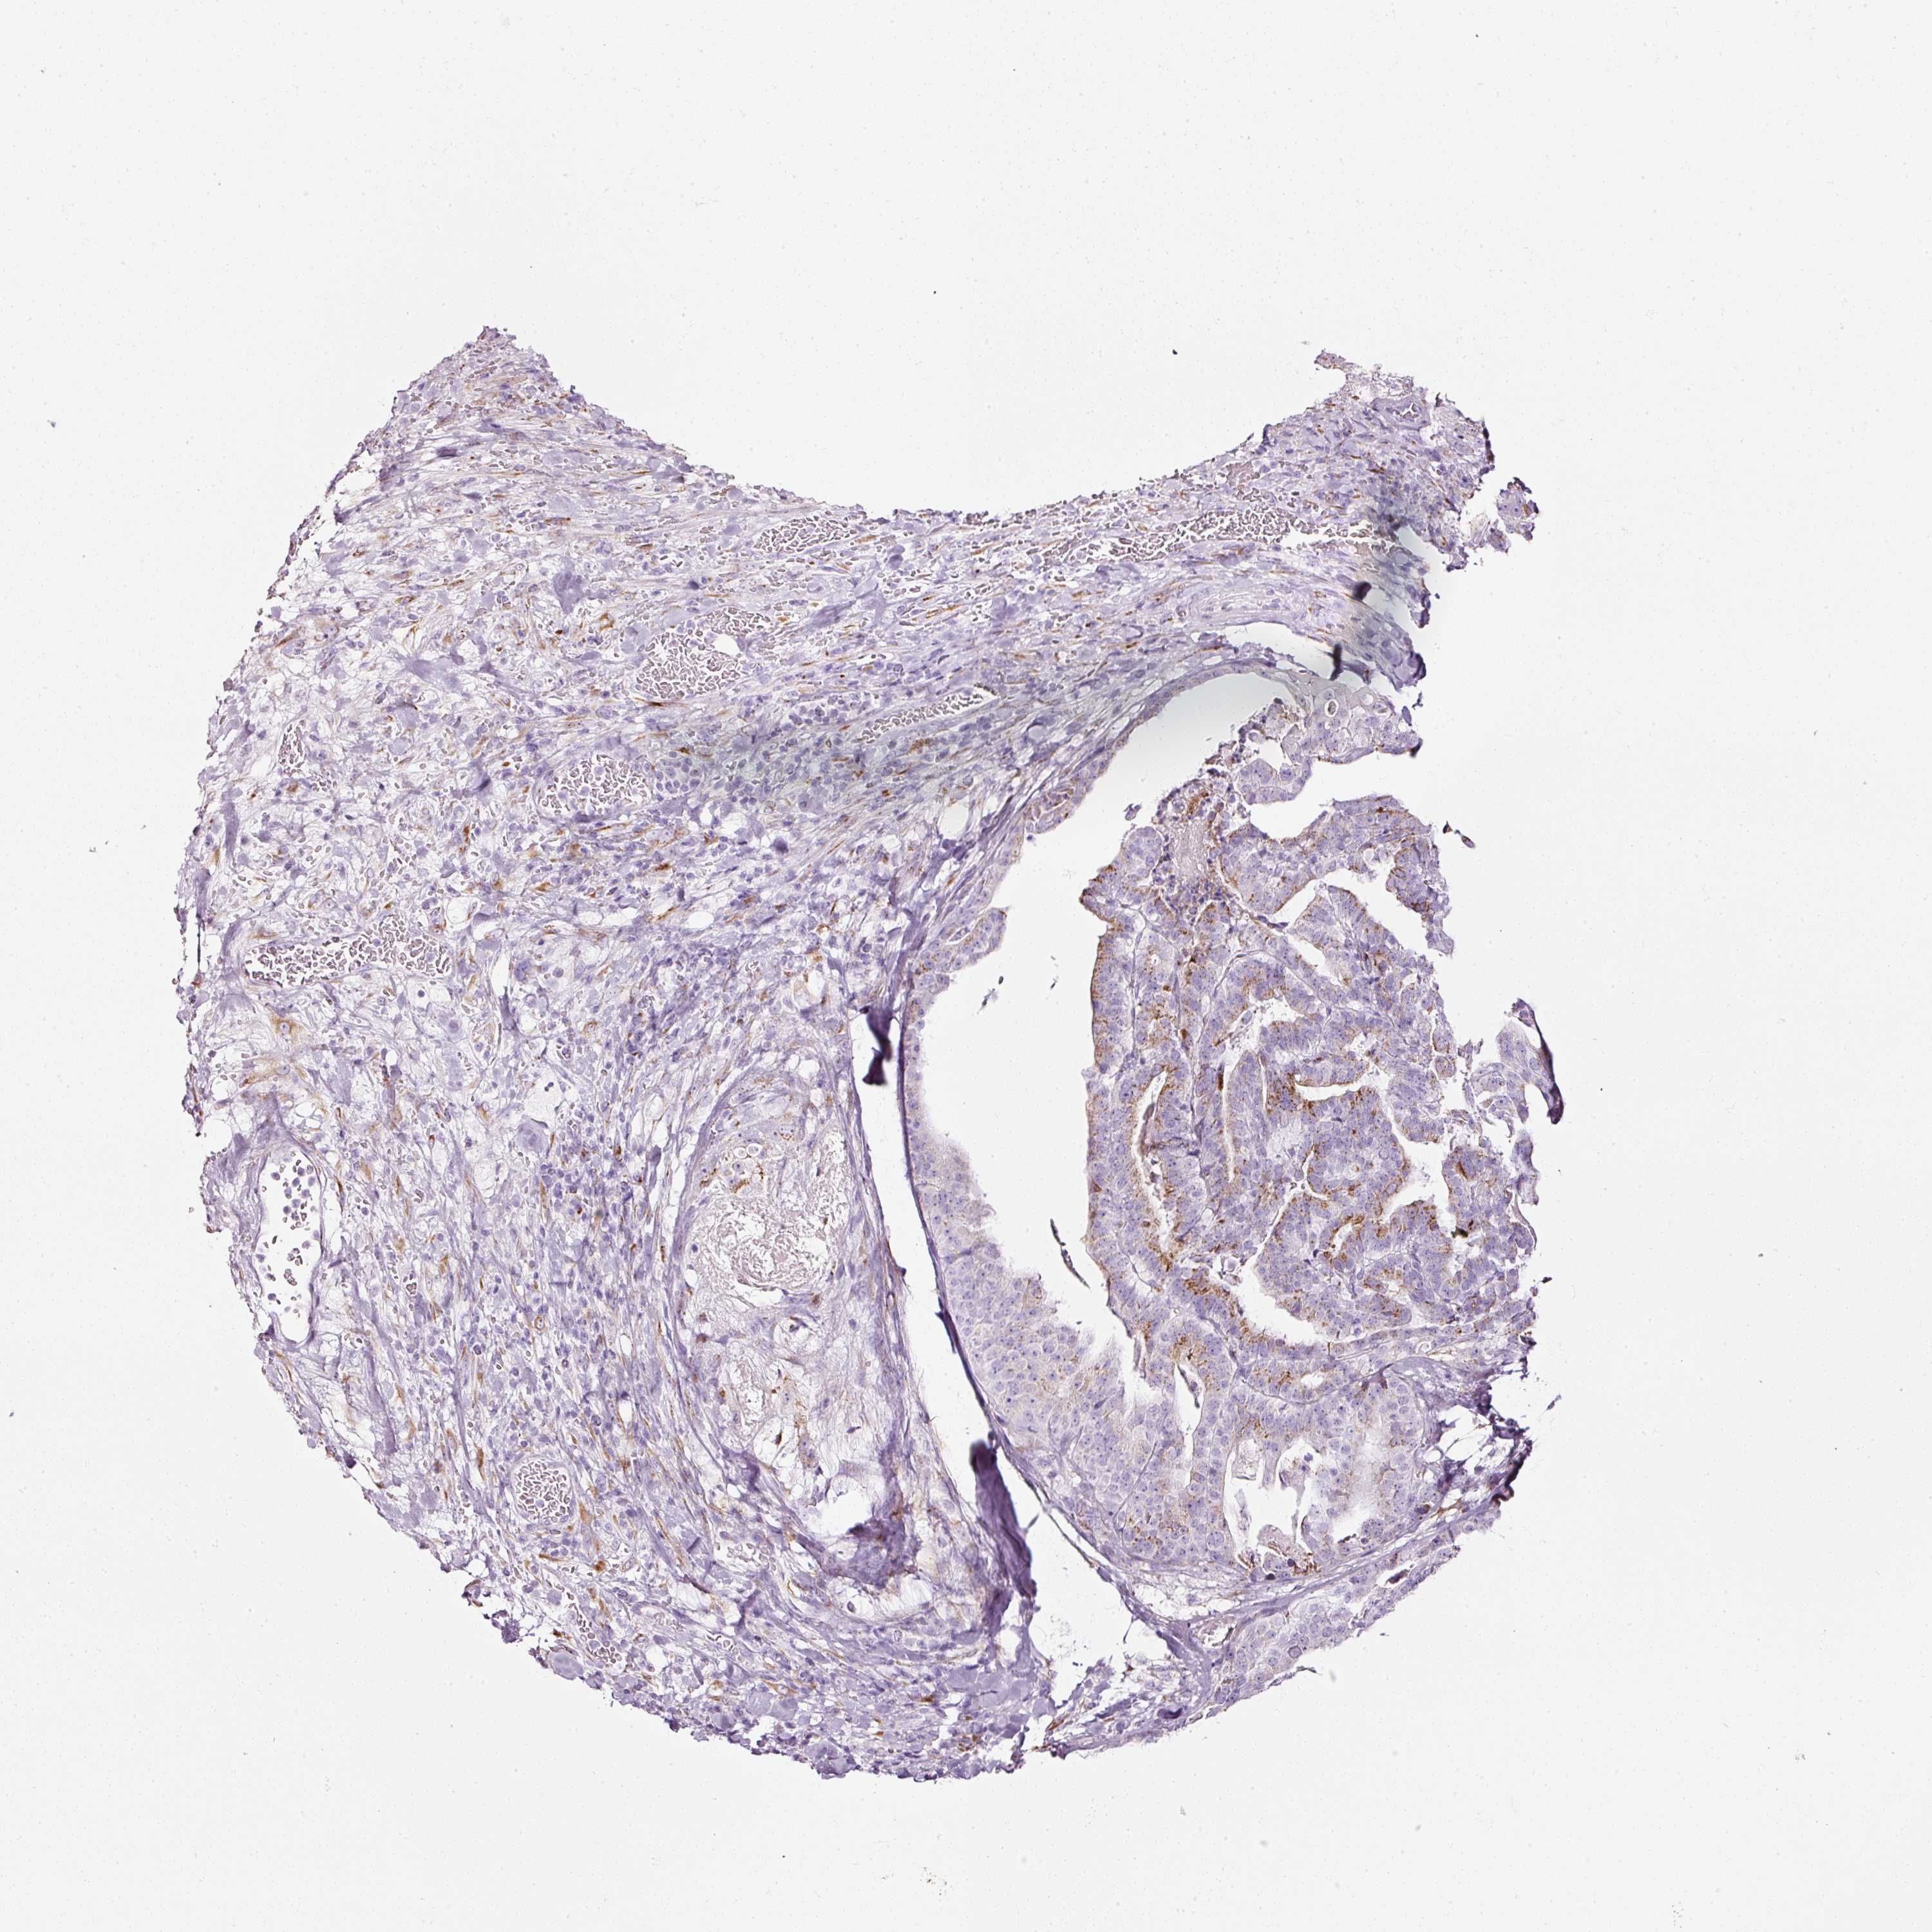

STOMACH CANCER - Protein expressioni

A mouse-over function shows sample information and annotation data. Click on an image to view it in a full screen mode. Samples can be filtered based on level of antibody staining by selecting one or several of the following categories: high, medium, low and not detected. The assay and annotation is described here.

Note that samples used for immunohistochemistry by the Human Protein Atlas do not correspond to samples in the TCGA dataset.

Antibody stainingi

Antibody staining in the annotated cell types in the current human tissue is reported as not detected, low, medium, or high, based on conventional immunohistochemistry profiling in selected tissues. This score is based on the combination of the staining intensity and fraction of stained cells.

Each image is clickable and will lead to virtual microscopy that enables deeper exploration of all samples and also displays staining intensity scores, fraction scores and subcellular localization as well as patient and tissue information for each sample.

Antibody HPA011249

Antibody CAB015227

Staining

High

Medium

Low

Not detected

Intensity

Strong

Moderate

Weak

Negative

Quantity

>75%

75%-25%

<25%

None

Location

Nuclear

Cytoplasmic/membranous

Cytoplasmic/membranous,nuclear

Adenocarcinoma, NOS